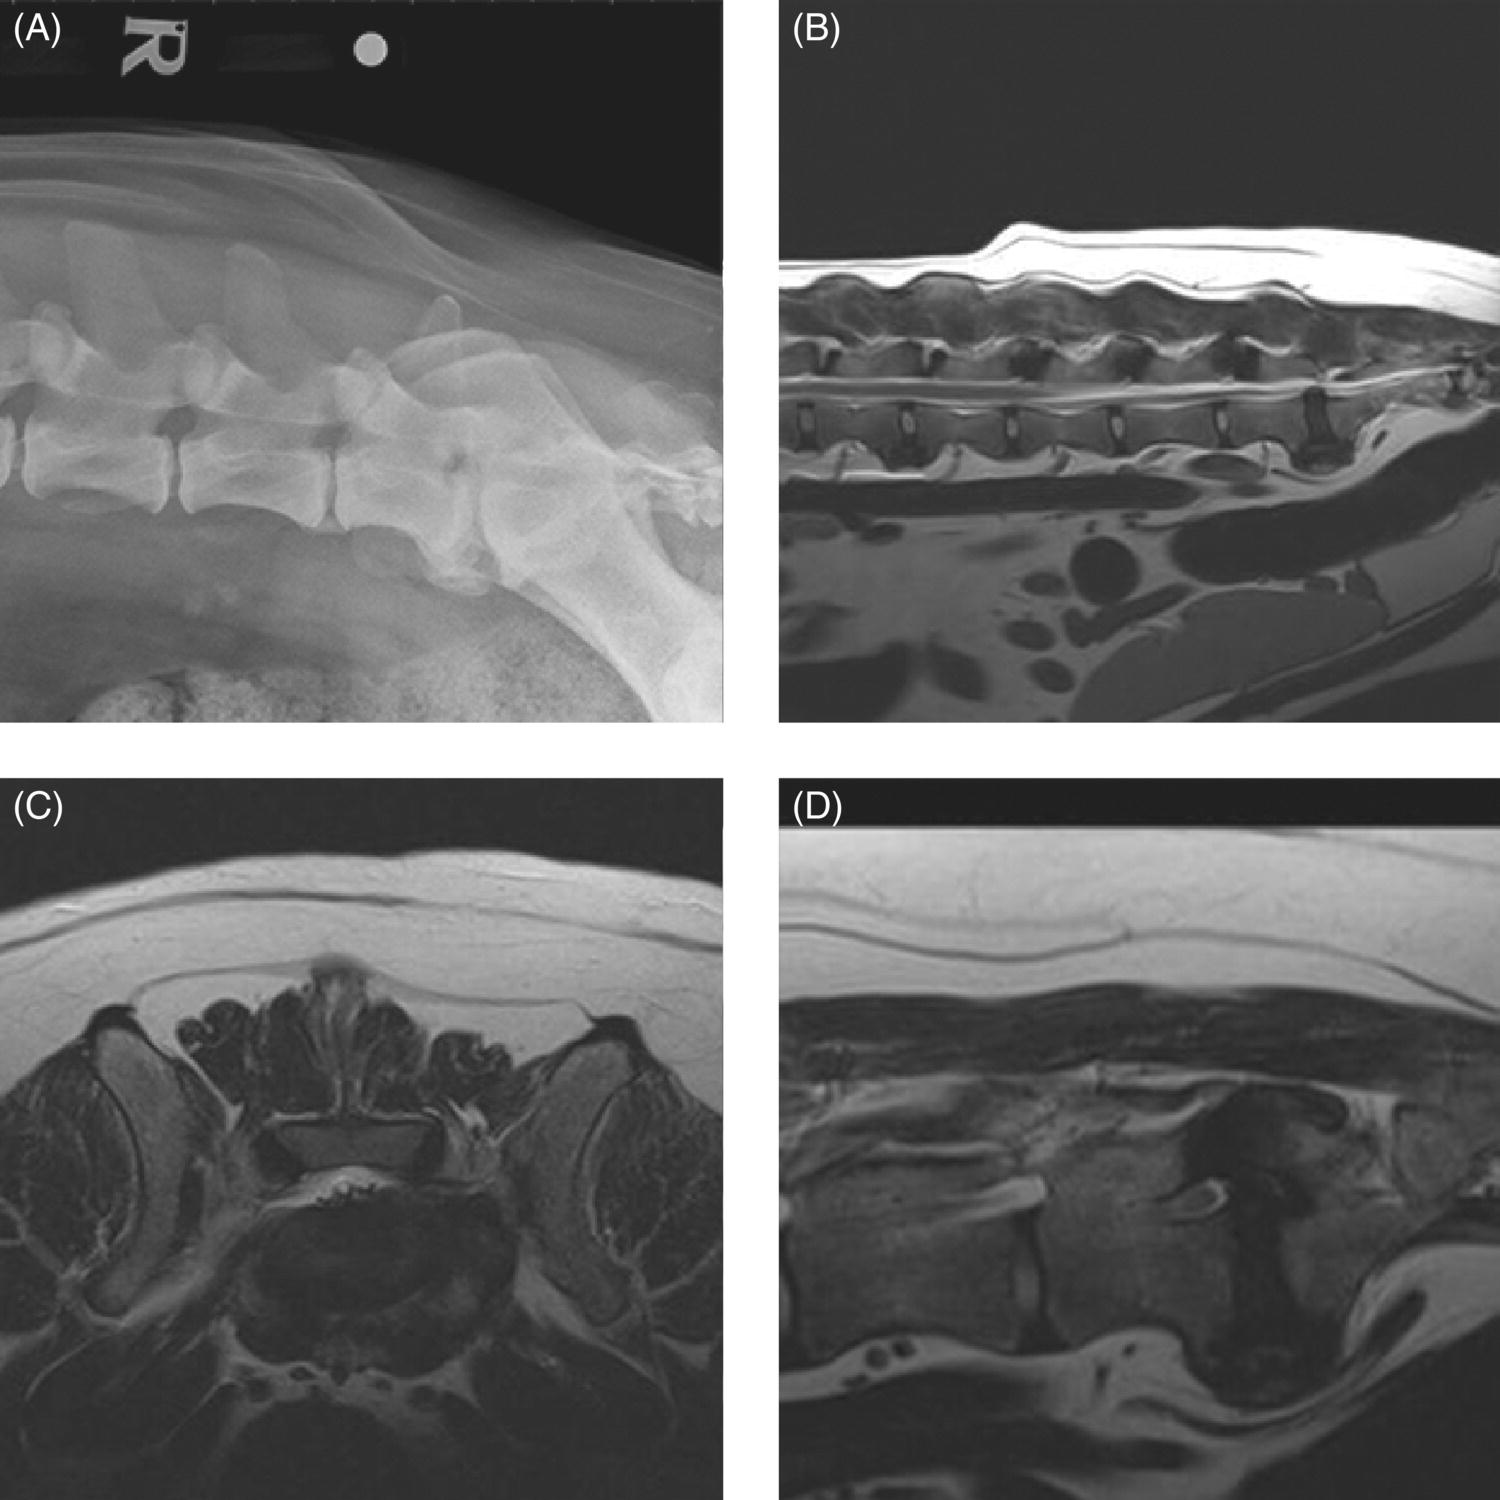

From www.researchgate.net

Ventrodorsal projection of the lumbosacral area in a dog with the Lumbosacral In Dogs Lumbosacral disease is also known as cauda equina syndrome. The most common symptom of lumbosacral stenosis is pain. Lumbosacral stenosis is a spinal condition of dogs (and less commonly cats) that resembles a ‘slipped disc’ or ‘sciatica’ in people. Large breeds of dogs are more commonly affected with lumbosacral stenosis, and german shepherd dogs and border collies appear to be. Lumbosacral In Dogs.

Ventrodorsal projection of the lumbosacral area in a dog with the Lumbosacral In Dogs Lumbosacral stenosis is a spinal condition of dogs (and less commonly cats) that resembles a ‘slipped disc’ or ‘sciatica’ in people. The most common symptom of lumbosacral stenosis is pain. Back pain is the most common sign of this condition in pets, although. The lower spine is the area that is most affected. Spinal stenosis, and more specifically lumbosacral stenosis,. Lumbosacral In Dogs.

Extended ventrodorsal radiograph of the lumbosacral joint and pelvis of Lumbosacral In Dogs Spinal stenosis, and more specifically lumbosacral stenosis, is a painful disease affecting the lower level of the spinal cord of a dog and can cause urinary, bowel, and walking problems. Lumbosacral stenosis is a spinal condition of dogs (and less commonly cats) that resembles a ‘slipped disc’ or ‘sciatica’ in people. Lumbosacral disease is also known as cauda equina syndrome.. Lumbosacral In Dogs.

Ventrodorsal projection of the lumbosacral area in a normal dog with Lumbosacral In Dogs Degenerative lumbosacral stenosis (dlss) is the most common cause of compression of the cauda equina and seventh lumbar (l7) nerve roots in. In the beginning, you may notice your dog has hind end stiffness that. The most common symptom of lumbosacral stenosis is pain. Canine lumbosacral disease is the term used for a group of diseases affecting the lumbosacral intervertebral. Lumbosacral In Dogs.